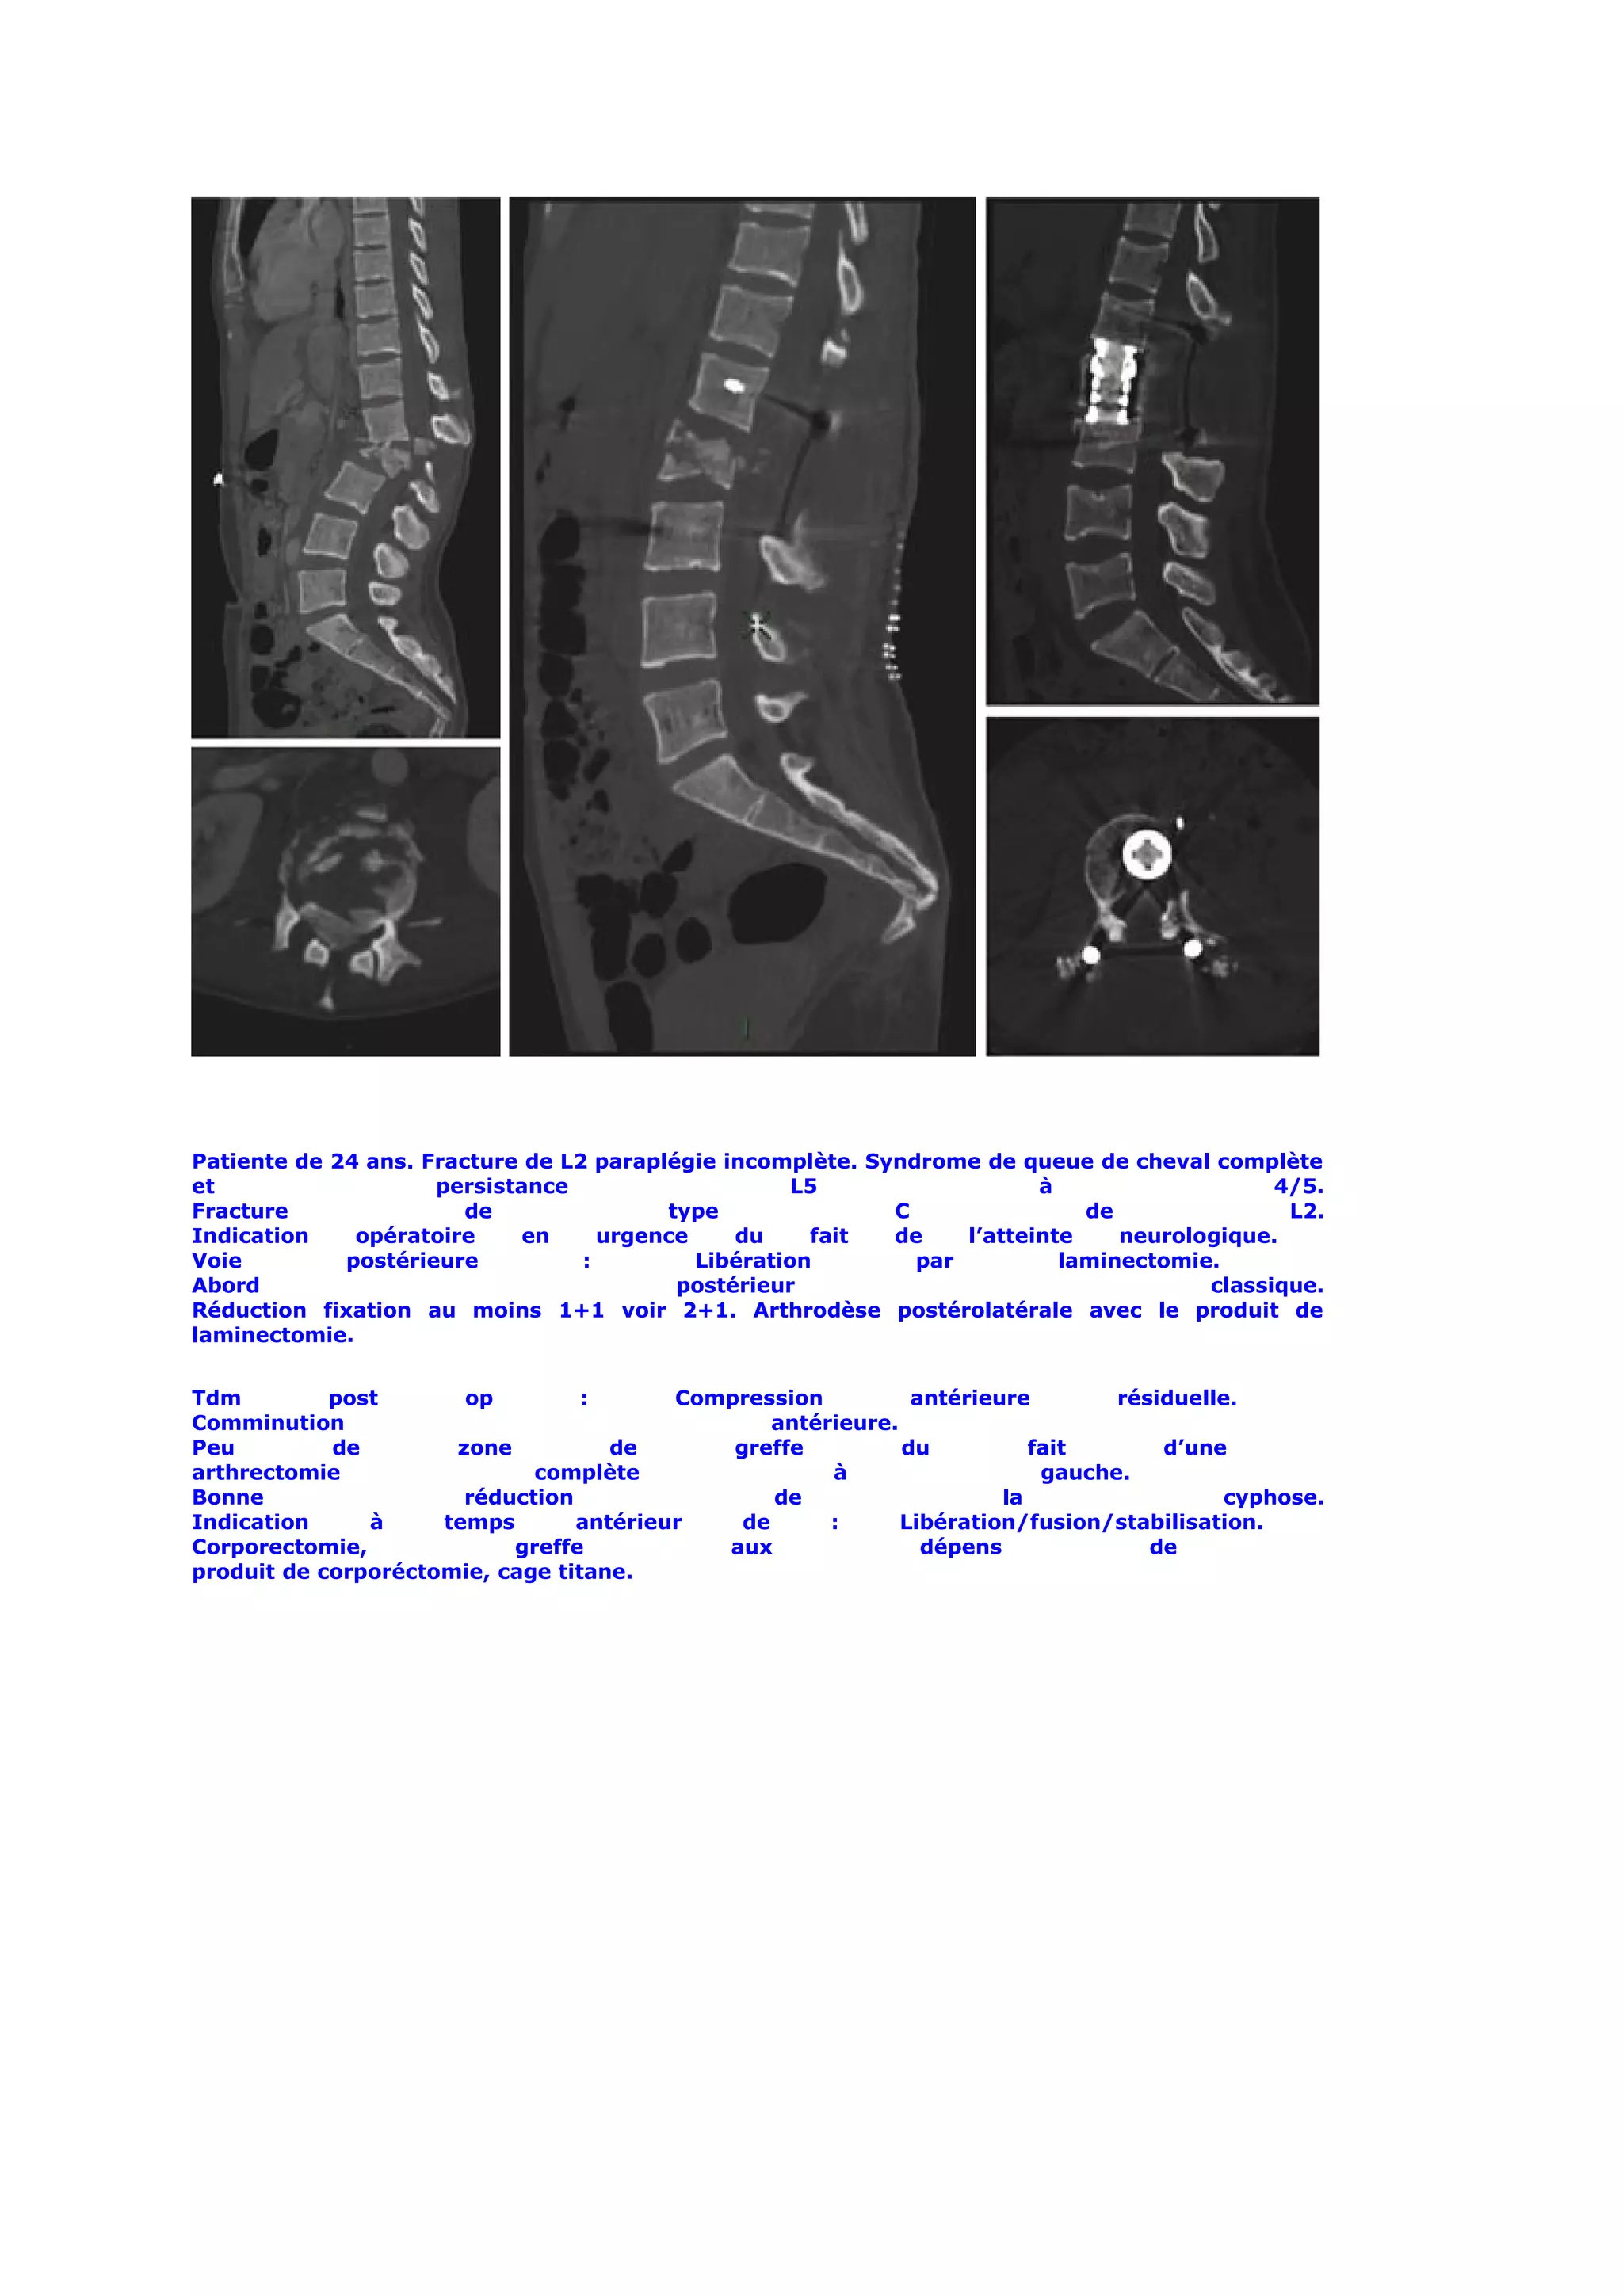

Patiente de 24 ans. Fracture de L2 paraplégie incomplète. Syndrome de queue de cheval complète

et                   persistance                     L5                  à                   4/5.

Fracture                de               type               C                de               L2.

Indication    opératoire     en     urgence    du     fait  de    l’atteinte    neurologique.

Voie         postérieure          :         Libération        par          laminectomie.

Abord                                     postérieur                                   classique.

Réduction fixation au moins 1+1 voir 2+1. Arthrodèse postérolatérale avec le produit de

laminectomie.

Tdm         post       op         :      Compression          antérieure        résiduelle.

Comminution                                      antérieure.

Peu         de        zone          de       greffe          du          fait       d’une

arthrectomie                 complète                 à                   gauche.

Bonne                  réduction                 de                   la                 cyphose.

Indication     à     temps       antérieur    de      :      Libération/fusion/stabilisation.

Corporectomie,             greffe           aux                dépens              de

produit de corporéctomie, cage titane.